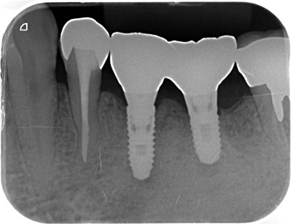

インプラント治療とは

インプラントとは、体内に埋め込まれる器具の総称で、医療目的で広く使用され、骨折などの治療で骨を固定するためのボルトや心臓ペースメーカなどもこれに当たります。

歯科の場合は、歯を失った時にそこを補うために、顎骨に人工歯根を埋め込んで、噛めるようにするインプラント治療が、広くおこなわれています。

インプラントの構造

一般的に、インプラントは3つのパーツから成っています。

(1) インプラント本体(人工歯根)

顎骨に埋め込まれる部分です。ネジ状の形態をしており、骨としっかりと結合して一体化します。

(2) アバットメント(土台)

フィクスチャーと上部構造をつなぐ、接合部分です。

アバットメントとフィクスチャーは専用のネジで締結します。

(3) 上部構造(被せ物)

被せ物の部分です。

アバットメントと専用のネジで締結する場合と、アバットメントに歯科用セメントで合着する場合があります。

主にジルコニアという強度の高いセラミックで作製することが多いです。

上部構造は取り外すことができますので、もし欠けたり割れたりした場合でも、この部分のみの修理や、作り直すことができます。